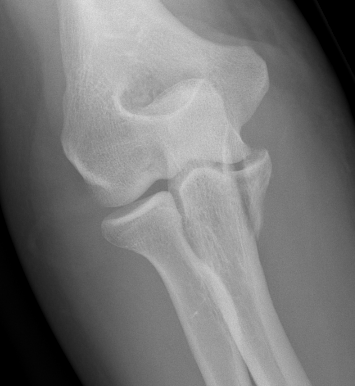

Elbow dislocation with coronoid process fracture

Coronoid process

Coronoid is the most important portion of ulno-humeral articulation

- provides anterior buttress

- attachment of capsule and brachialis

- anterior band of the MCL attaches to it

Regan and Morrey classification of transverse coronoid fractures

Elbow stability related to size of coronoid fragment